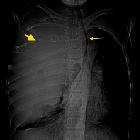

Ewingsarkom der Brustwand

Ewing sarcomas are the second most common malignant primary bone tumors of childhood after osteosarcoma, typically arising from medullary cavity with invasion of the Haversian system. They usually present as moth-eaten destructive permeative lucent lesions in the shaft of long bones with large soft tissue component without osteoid matrix and typical onion skin periostitis. It may also involve flat bones and appears sclerotic in up to 30% of cases.